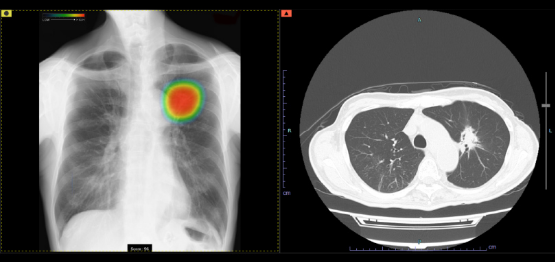

当院では、富士フイルム社のAI診断支援システム「CXR-AID」を導入しています。

このAIは胸部レントゲン画像を自動で解析し、

病変が疑われる部分を検出・表示して、医師の診断をサポートします。

AIによるサポートで、診断の精度向上と見落とし防止が期待できます。

異常が見つかった場合は、CTなど精密検査を行い、確定診断へとつなげています。